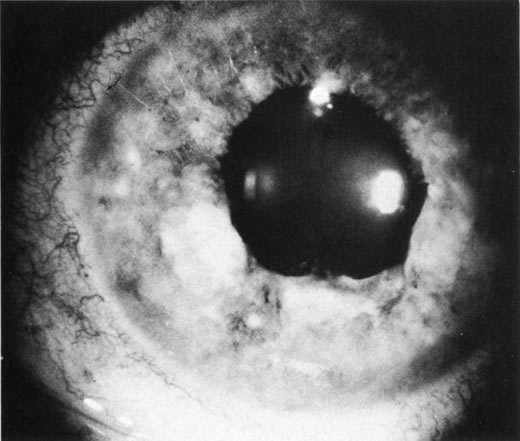

Unfortunately, imaging studies are not always diagnostic. The A- and B-scans shown in Figures 3 and 4 were from a patient with unilateral media opacity referred for evaluation and treatment of a presumed uveal melanoma. Occasionally, if the cataractous lens is scanned tangentially, artifact can occur. A repeat ultrasound at our institution was negative for tumor, and the referral ophthalmologist who performed a cataract extraction noted that no tumor was present and that the patient has an excellent visual outcome. In contrast, the patient shown in Figure 5 was referred with a presumed uveal melanoma with secondary inflammation and a history similar to that described for the patient shown in Figure 111 Ultrasound and CT examinations were not diagnostic. Because the eye was blind and painful, it was enucleated, and an extremely necrotic uveal melanoma was noted histologically. In some necrotic melanomas, the fundus cannot be visualized and the diagnosis cannot be established with imaging studies. Very rarely, a necrotic uveal melanoma can produce sufficient pigment dispersion into the vitreous to obscure the correct diagnosis.12